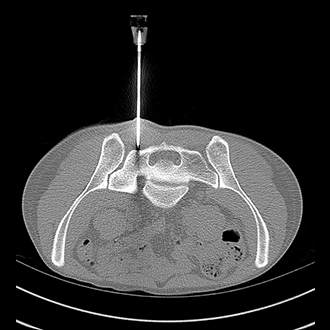

BIOPSY

Biopsy and Drainage

We at Gokul Diagnostic and Scan Centre provide facilities for various radiological interventions under the guidance of CT Scan, XrayFluroscopy and Ultrasonography.

As we have availability of various modalities we choose from CT or Sonography guidance whichever is best suited for the patient under given clinical scenario.

We have a team of dedicated radiologists who are highly trained in doing imaging based interventions.

We have excellent success rates with patient safety being our priority.

We Perform :

1. CT/USG guided biopsies.

2. CT/USG guided drainages.

3. FNAC